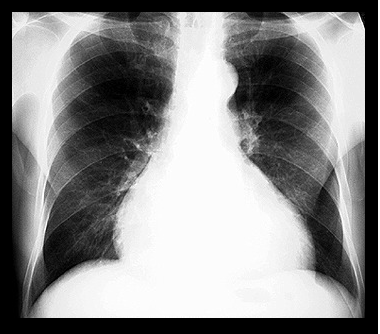

CARDIOMIOPATIILE

CARDIOMIOPATIILE Cardiomiopatiile sunt un grup heterogen de boli caracterizate prin afectarea predominanta si initiala a miocardului, insotite de disfunctie cardiaca. Definitia are un sens restrictiv, deoarece exclude afectarea miCiteste tot ... 8775 cuvinte

ANEVRISM SACCIFORM DE CROSA AORTICA LA UN PACIENT ASIMPTOMATIC SI PROBLEMELE DE CONDUITA TERAPEUTICA

ANEVRISM SACCIFORM DE CROSA AORTICA LA UN PACIENT ASIMPTOMATIC SI PROBLEMELE DE CONDUITA TERAPEUTICA Definitie: Anevrismul de aorta reprezinta dilatarea aortei de peste 1,5 ori diametrul aortei corespunzator segmentului respectCiteste tot ... 1147 cuvinte

BOLILE APARATULUI CARDIO-VASCULAR

BOLILE APARATULUI CARDIO-VASCULAR Aparatul cardio-vascular este format din inima, vase sanguine si limfatice. Inima este un organ tetracameral (doua atrii si doua ventricule), care pompeaz�Citeste tot ... 820 cuvinte